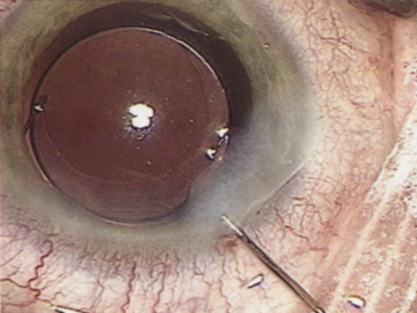

ANTERIOR CAPSULOTOMY

One of the most beneficial techniques developed over the last decade is capsulorrhexis. A continuous curvilinear anterior capsular opening helps prevent intraoperative and postoperative complications. With capsulorrhexis, mechanical strength of the capsular opening is superior to that in a can-opener capsulotomy; thus, a tear to the posterior capsule with subsequent vitreous loss is much less likely.96 Capsulorrhexis allows for nuclear manipulation with less risk of posterior capsule rupture. Cortex removal is made easier as well, because it becomes easier to differentiate cortical material from anterior capsule. Should a posterior capsular tear occur, sulcus fixation is more likely attainable with the presence of a clearly visible residual anterior capsular rim. Placement of both IOL haptics into the capsular bag is more certain with capsulorrhexis because the surgeon can more easily visualize the haptics gliding beneath the anterior capsular rim.

Capsulorrhexis can be performed with a cystitome, capsulorrhexis forceps, or combination-type instruments. Regardless of which instrument is used, several principles can help the surgeon successfully complete capsulorrhexis. It is important to maintain the anterior chamber, because making the chamber shallow increases tension on the zonules and causes the tear to run peripherally. The authors recommend the use of a viscoelastic agent for maintaining chamber depth and, of course, for endothelial protection. Therefore, if the tear begins to run peripherally, the surgeon should redeepen the anterior chamber before attempting to redirect the tear. Additionally, folding the capsule margin can aid the surgeon in redirecting the tear more accurately (Fig. 10).

Fig. 10. The capsulorrhexis tear is more easily redirected by folding the capsule over, in advance of the tear.